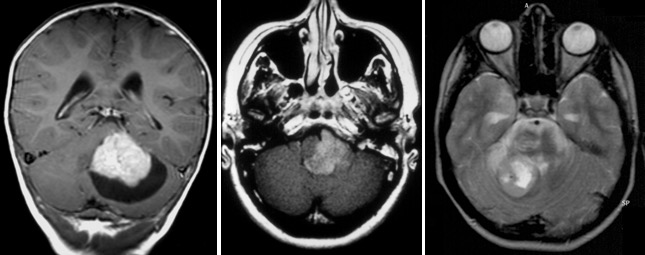

elle peut être très évocatrice, montrant une tumeur spontanément hyperdense en scanner, avec une prise de contraste hétérogène et une hypercellularité bien montrée par la séquence en diffusion.

l’aspect radiologique peut cependant être trompeur.

on recherche systématiquement des métastase par l‘IRM cranio-spinale.